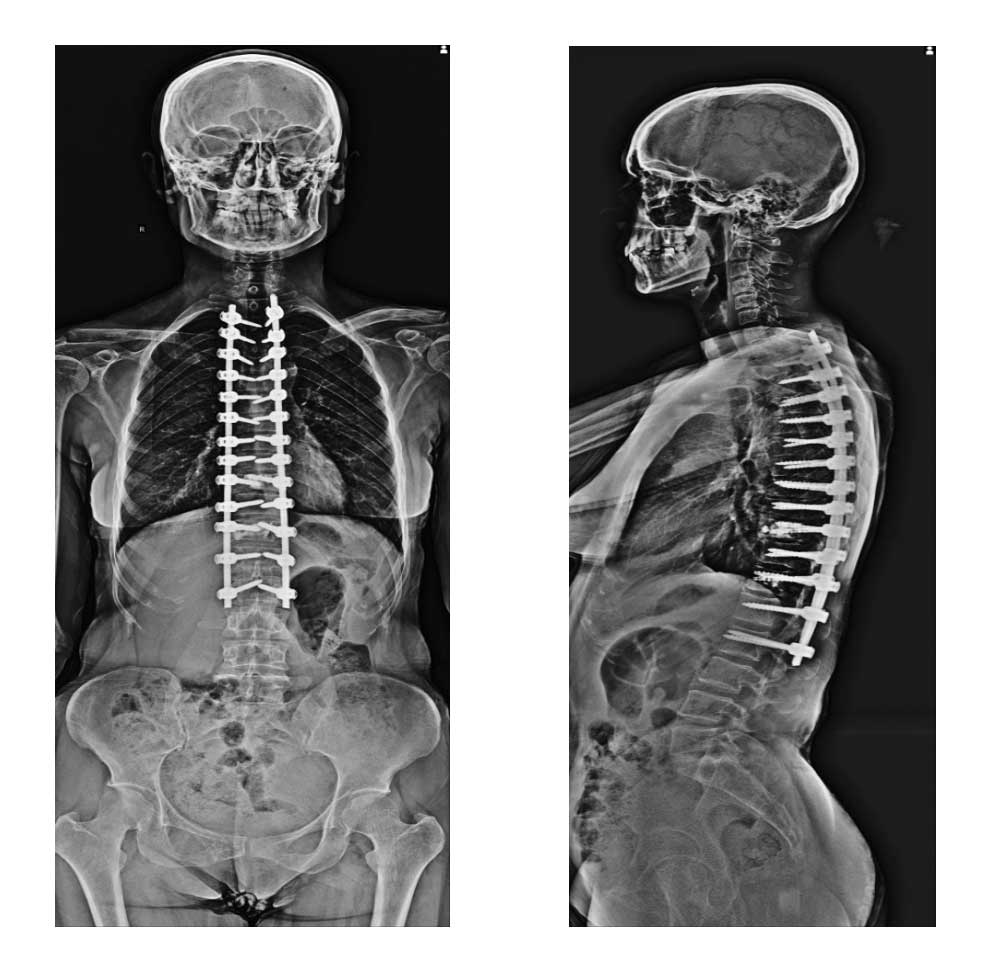

Ameliyat Sonrası: Röntgende boş olan omurga kemiklerinin içini çimento ile doldurulup kamburluğun düzeltilip vidalama ile sabitlenmesi görülmekte.